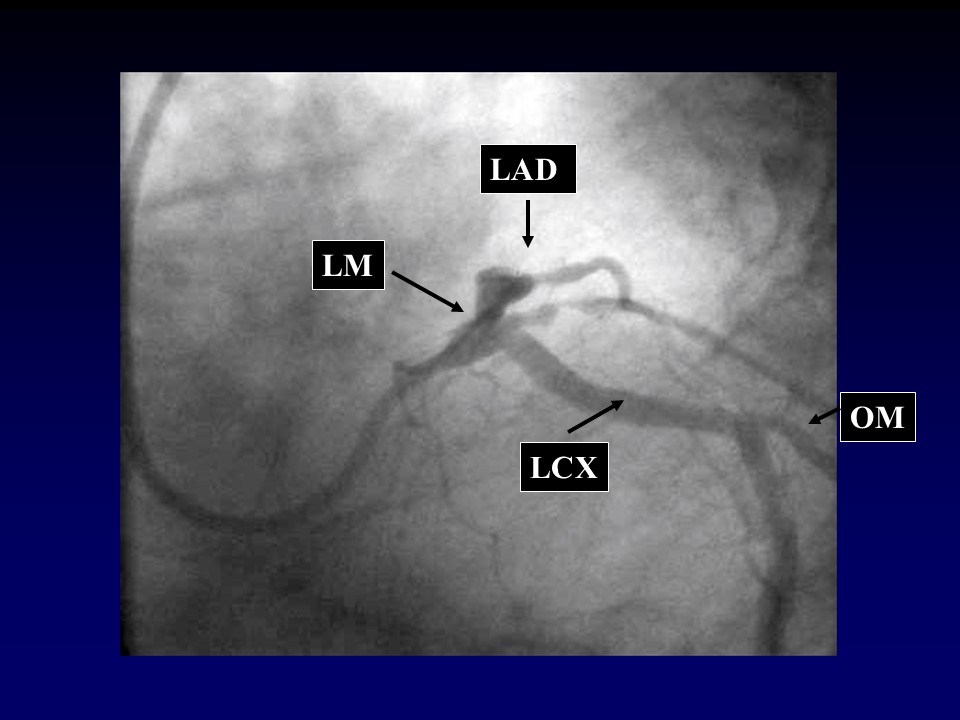

冠脉造影的规范操作PPT